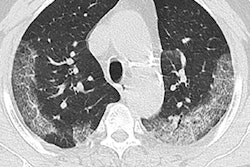

Intelligent Evaluation System of Chest CT uses algorithms to quantitatively analyze key imaging features from CT scans to detect and assess COVID-19, according to the vendor. The software grades the severity of pneumonia diseases using lesion morphology, range, and density. It can also quantify the cumulative pneumonia load of the disease, the company said.

The system can automatically detect the lesion area and perform its analysis in 2 to 3 seconds, Yitu Healthcare said. Shanghai Public Health Clinical Center shared its experience with using the software in an article posted on its official WeChat platform on February 4.